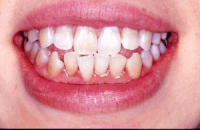

※写真は神経がない歯にブライトホワイトを一回行った写真です。右の前歯2本の神経がありませんが、歯の内部に汚れがなかったため、表からのホワイトニングだけでかなり白くなっています(詰め物は白くなっていません)。